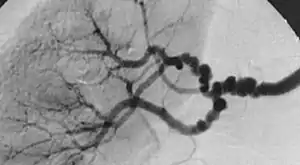

| The "string-of-beads" feature in multi-focal fibromuscular dysplasia. The sign is caused by areas of relative stenoses alternating with small aneurysms. | |

The second type, multi-focal fibroplasia, involves thickening of the media and collagen formation. It is typically reported as having the appearance of a ‘string of beads’ on angiographic review.[4] "The 'bead' component is often larger than the normal arterial lumen, and in a subset of patients with FMD, aneurysms are present that may require treatment."[4] The multi-focal subtype of FMD accounts for nearly 80% to 90% of all FMD cases.[4] (previously known as medial)